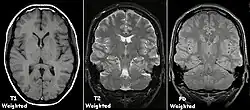

T1 e T2

Cada tecido retorna ao seu estado de equilíbrio após a excitação pelos processos independentes de T1 (spin-tretice) e T2 (spin-spin) de relaxamento. Para criar uma imagem ponderada em T1, a magnetização pode ser recuperada antes de medir o sinal MR, alterando o tempo de repetição (TR). Esta ponderação de imagem é útil para avaliar o córtex cerebral, identificando tecido adiposo, caracterizando lesões focais e, em geral, para obter informações morfológicas, bem como para imagens pós-contraste. Para criar uma imagem ponderada em T2, a magnetização pode decair antes de medir o sinal MR alterando o tempo de eco (TE). Esta ponderação de imagem é útil para detectar edema e inflamação, revelando lesões de substância branca e avaliando a anatomia zonal na próstata e no útero.

A exibição padrão de imagens de MRI é representar características de fluido em imagens em preto e branco, onde diferentes tecidos são os seguintes:

| Grupo | Sequência | Abreviatura | Física | Distinções clínicas principais | Exemplo |

|---|---|---|---|---|---|

| Eco de spin | Ponderado em T1 | T1 | Medição da relaxação spin-lattice usando um tempo de repetição (TR) curto e tempo de eco (TE) curto. |

Base padrão e comparação para outras sequências. |

![]() |

| Ponderado em T2 | T2 | Medição da relaxação spin-spin usando TR e TE longos |

|

![]() | |